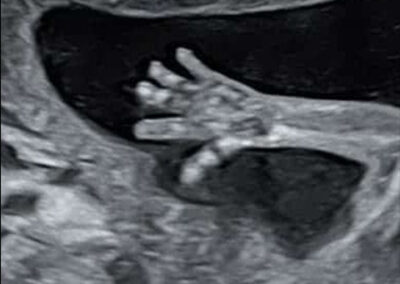

גלריה